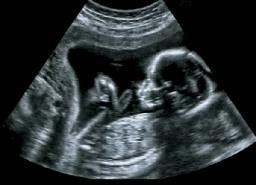

"The baby is already present and living. Abortion is a matter of the life or death of a human being made in God’s image ( Genesis 1:26–27 ; 9:6 ).

What does the Bible say about abortion? Simply put, abortion is murder . It is the killing of a human being created in the image of God." The whole article you can read it on